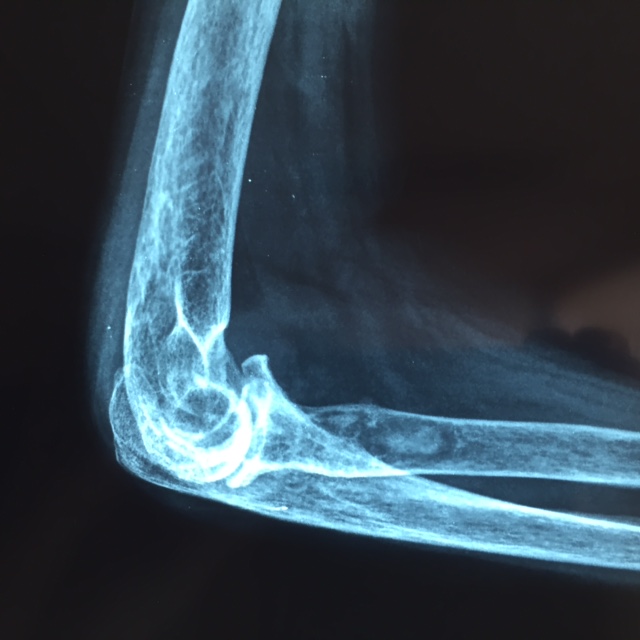

Le coude est une articulation reliant l’extrémité inférieure de l’humérus (trochlée) et l’extrémité supérieure des 2 os de l’avant bras (olécrane et tête radiale). Elle est maintenue par des muscles (stabilisateurs actifs : biceps, triceps, anconé et muscles extenseurs et fléchisseurs du poignet) et par des ligaments (stabilisateurs passifs : Ligament latéral externe, interne, antérieur, postérieur, annulaire ligament radio-cubital supérieur et capsule).

Le bilan radiologique (radiographies standards) permet de visualiser les lésions. Ce dernier montrera une destruction osseuse dans les cas d’arthrite inflammatoire évoluée (classification de Larsen), une disparition de l’interligne avec ostéophytose (arthrose), des lésions de fracture de la palette humérale ou de la tête radiale (classification de Masson) …

Un arthroscanner et éventuellement une IRM pourront être faits dans le cadre d’un bilan fracturaire ou de lésions inflammatoires, tumorales ou pour planifier la prothèse de coude.